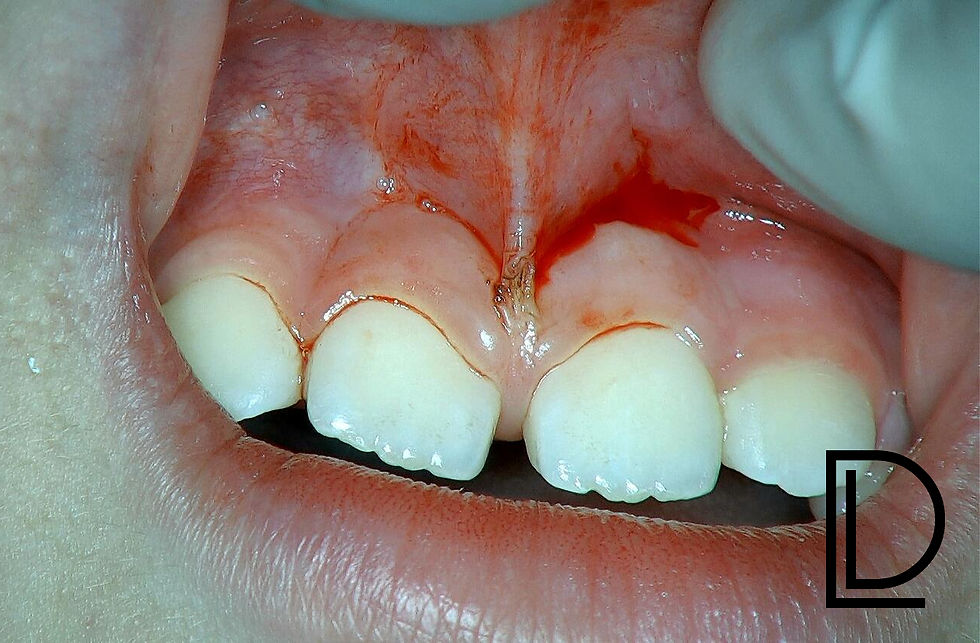

Upper anterior labial frenum is attached very high, close to the interdental papilla between teeth #11 and #21.

Frenum released under tension using 980nm diode laser.

Alveolar gingival attachment dissected.

Laser applied for final contouring and hemostasis.